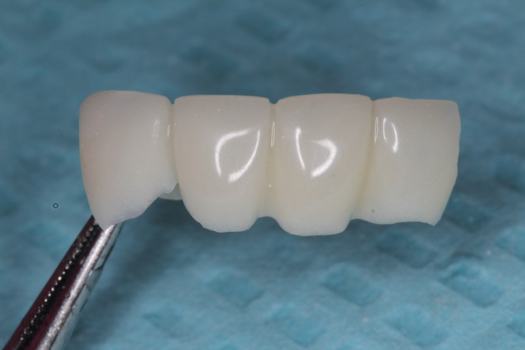

After completing an initial diagnostic appointment, a patient accepted three single-unit full-contour zirconia crowns that were milled from the digital impression and cut back for porcelain application. The application by a technician is analog dentistry. The ability of a dental laboratory to scan an analog crown-and-bridge impression is called converting an analog impression to a digital impression. The workflow after the conversion has become digitized. A dental model is virtually created with computer software, and a full crown proposal is fabricated for inspection virtually before the crown is milled (Figure 2). Due to the color of the digitized impression, the margins of the crown preparations are more easily and rapidly identified. The laboratory will also 3D print a working model, which will be used to develop the morphology of the final restoration by hand placement of porcelain (Figure 3). The decision to prescribe a full contour zirconia crown with cutback for porcelain application or complete full contour zirconia crowns lies solely on the attending dentist.9 A discussion with the patient before preparation of the teeth is imperative. After the discussion, the patient requested the zirconia copings with cutback and porcelain application for the posterior crowns (Figure 4 and Figure 5).

Fig 4. Zirconia with cutback for porcelain application.

Figure 4

Fig 5. Occlusal view of completed zirconia with porcelain application on teeth Nos. 29, 30, and 31.

Figure 5